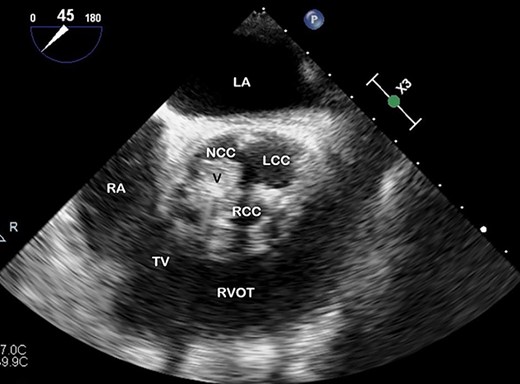

TOE, short axis demonstrating a vegetation (V) on the right coronary cusp (RCC; 11 × 8 mm) and on the non-coronary cusp (NCC; 15 × 11 mm); LCC, left coronary cusp; LA, left atrium; RA, right atrium; TV, tricuspid valve; RVOT, right ventricular outflow tract.